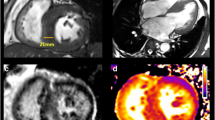

In the future, 3D-STE may contribute more to global and regional myocardial function evaluation, as well as to tissue characterization in various pathologic substrates and HCM (Fig. 5) [77]. Software improvements, including spatial and temporal resolution optimization, along with decrease of intervendor bias are crucial steps towards this direction [78, 80].

Late gadolinium-enhanced (LGE) cardiovascular magnetic resonance images (upper panels) and longitudinal strain bull’s eyes (lower panels) calculated by means of two-dimensional (2D) and three-dimensional (3D) deformation imaging. Evident is the correlation between fibrosis position indicated by LGE (arrows) and the functional impairment as highlighted by 2D and 3D longitudinal strain (blue areas show greater impairment)